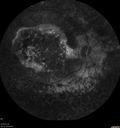

80 year old man Diagnosed at age 12 with retinitis pigmentosa. His central vision has been poor for a long time. He had surgery for nystagmus 3 times. He has worn glasses ever since he was 3 and he was bumping into walls when he was little. Night blindness was noticed by his mother at a young.

Mutations were confirmed in NR2E3 (Enhanced S Cone Syndrome)

VA OD HM; OS 6/200